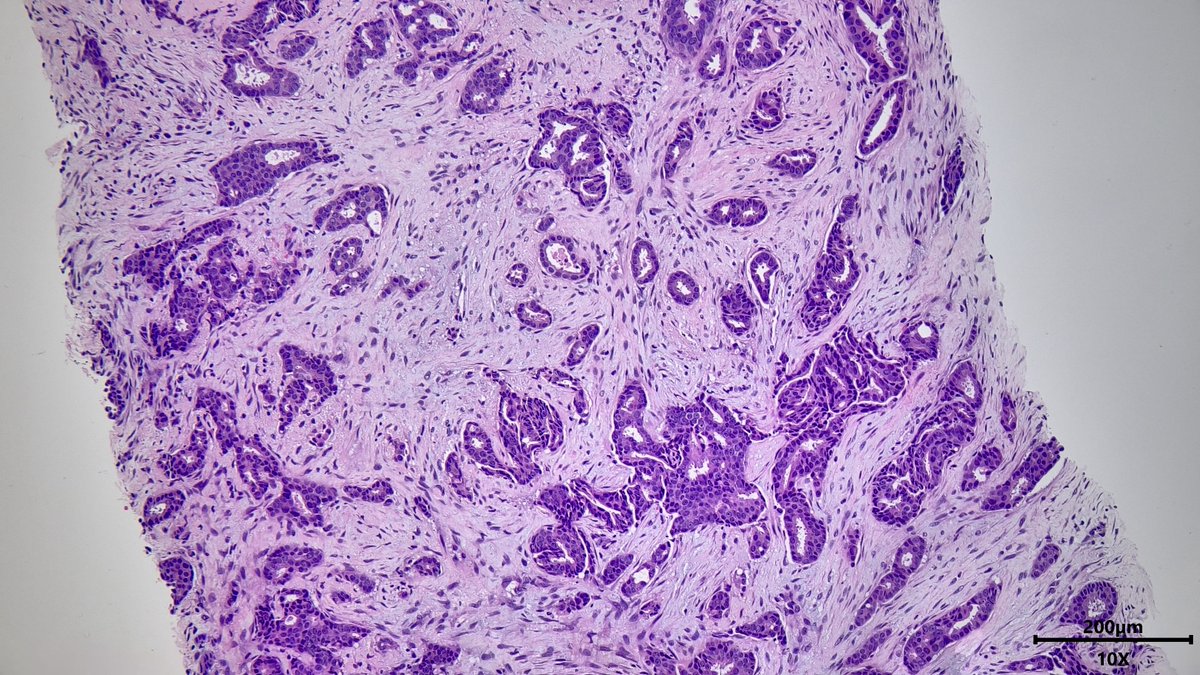

Nasal mass in young male #ENTPath #PathX What is your differential diagnosis? Which stain(s) are confirmatory? @Pathoutlines @UMichPath

MeredithKHerman's tweet image. Nasal mass in young male #ENTPath #PathX

What is your differential diagnosis?

Which stain(s) are confirmatory?